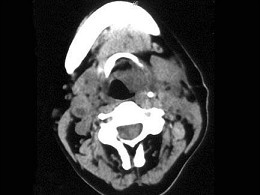

女,54岁,喉部异物感约3个月,PE:左侧声带固定,可见肿物,CT如图,最可能的诊断是()

A.喉部乳头状瘤

B.喉癌

C.喉部血管瘤

D.慢性增生性喉炎

E.增生型喉结核

女,54岁,喉部异物感约3个月,PE:左侧声带固定,可见肿物,CT如图,最可能的诊断是()<img border="0" style="width: 260px;

[单选题]女,54岁,喉部异物感约3个月,PE:左侧声带固定,可见肿物,CT如图,最可能的诊断是()A.喉部乳头状瘤B.喉癌C.喉部血管瘤D.慢性增生性喉炎E.

[单选题]女,54岁,喉部异物感约3个月,PE:左侧声带固定,可见肿物,CT如图,最可能的诊断是()A . 喉部乳头状瘤B . 喉癌C . 喉部血管瘤D . 慢性增生性喉炎E . 增生型喉结核

女、54岁,鼻咽部异物感约三个月,PE:左侧声带固定,可见肿物,CT如图所示,应诊断为()<img border="0" style="width: 182px;

[单选题]女、54岁,鼻咽部异物感约三个月,PE:左侧声带固定,可见肿物,CT如图所示,应诊断为()A.喉部乳头状瘤B.喉癌C.喉部血管瘤D.慢性增生性喉炎E.

[单选题]女,54岁,鼻咽部异物感约3个月,PE:左侧声带固定,可见肿物,CT如图所示,应诊断为()。A . 喉部乳头状瘤B . 喉癌C . 喉部血管瘤D . 慢性增生性喉炎E . 增生型喉结核

[单选题]女,54岁,鼻咽部异物感约3个月,PE:左侧声带固定,可见肿物,CT如图所示,应诊断为 ( )A.喉部乳头状瘤B.喉癌C.喉部血管瘤D.慢性增生性喉炎E.增生型喉结核

[单选题]女、54岁,鼻咽部异物感约三个月,PE:左侧声带固定,可见肿物,CT如图所示,应诊断为()A .喉部乳头状瘤B .喉癌C .喉部血管瘤D .慢性增生性喉炎E .增生型喉结核